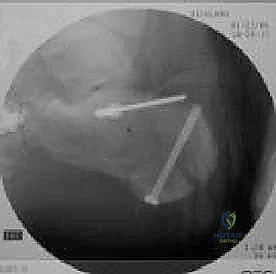

4. التثبيت المؤقت

يتم استخدام أسلاك معدنية دقيقة لتثبيت الشظايا في مكانها مؤقتاً، ثم يتم التحقق من دقة الرد باستخدام جهاز الأشعة السينية داخل غرفة العمليات (C-arm) لضمان عدم وجود أي انزياح ولو بمليمتر واحد.

صور إضافية من داخل غرفة العمليات توضح دقة الإجراء

توضح الصور التالية مدى تعقيد الجراحة والدقة التي يتطلبها تثبيت عظم الكعب، والتي يعكسها التميز الجراحي للأستاذ الدكتور محمد هطيف: